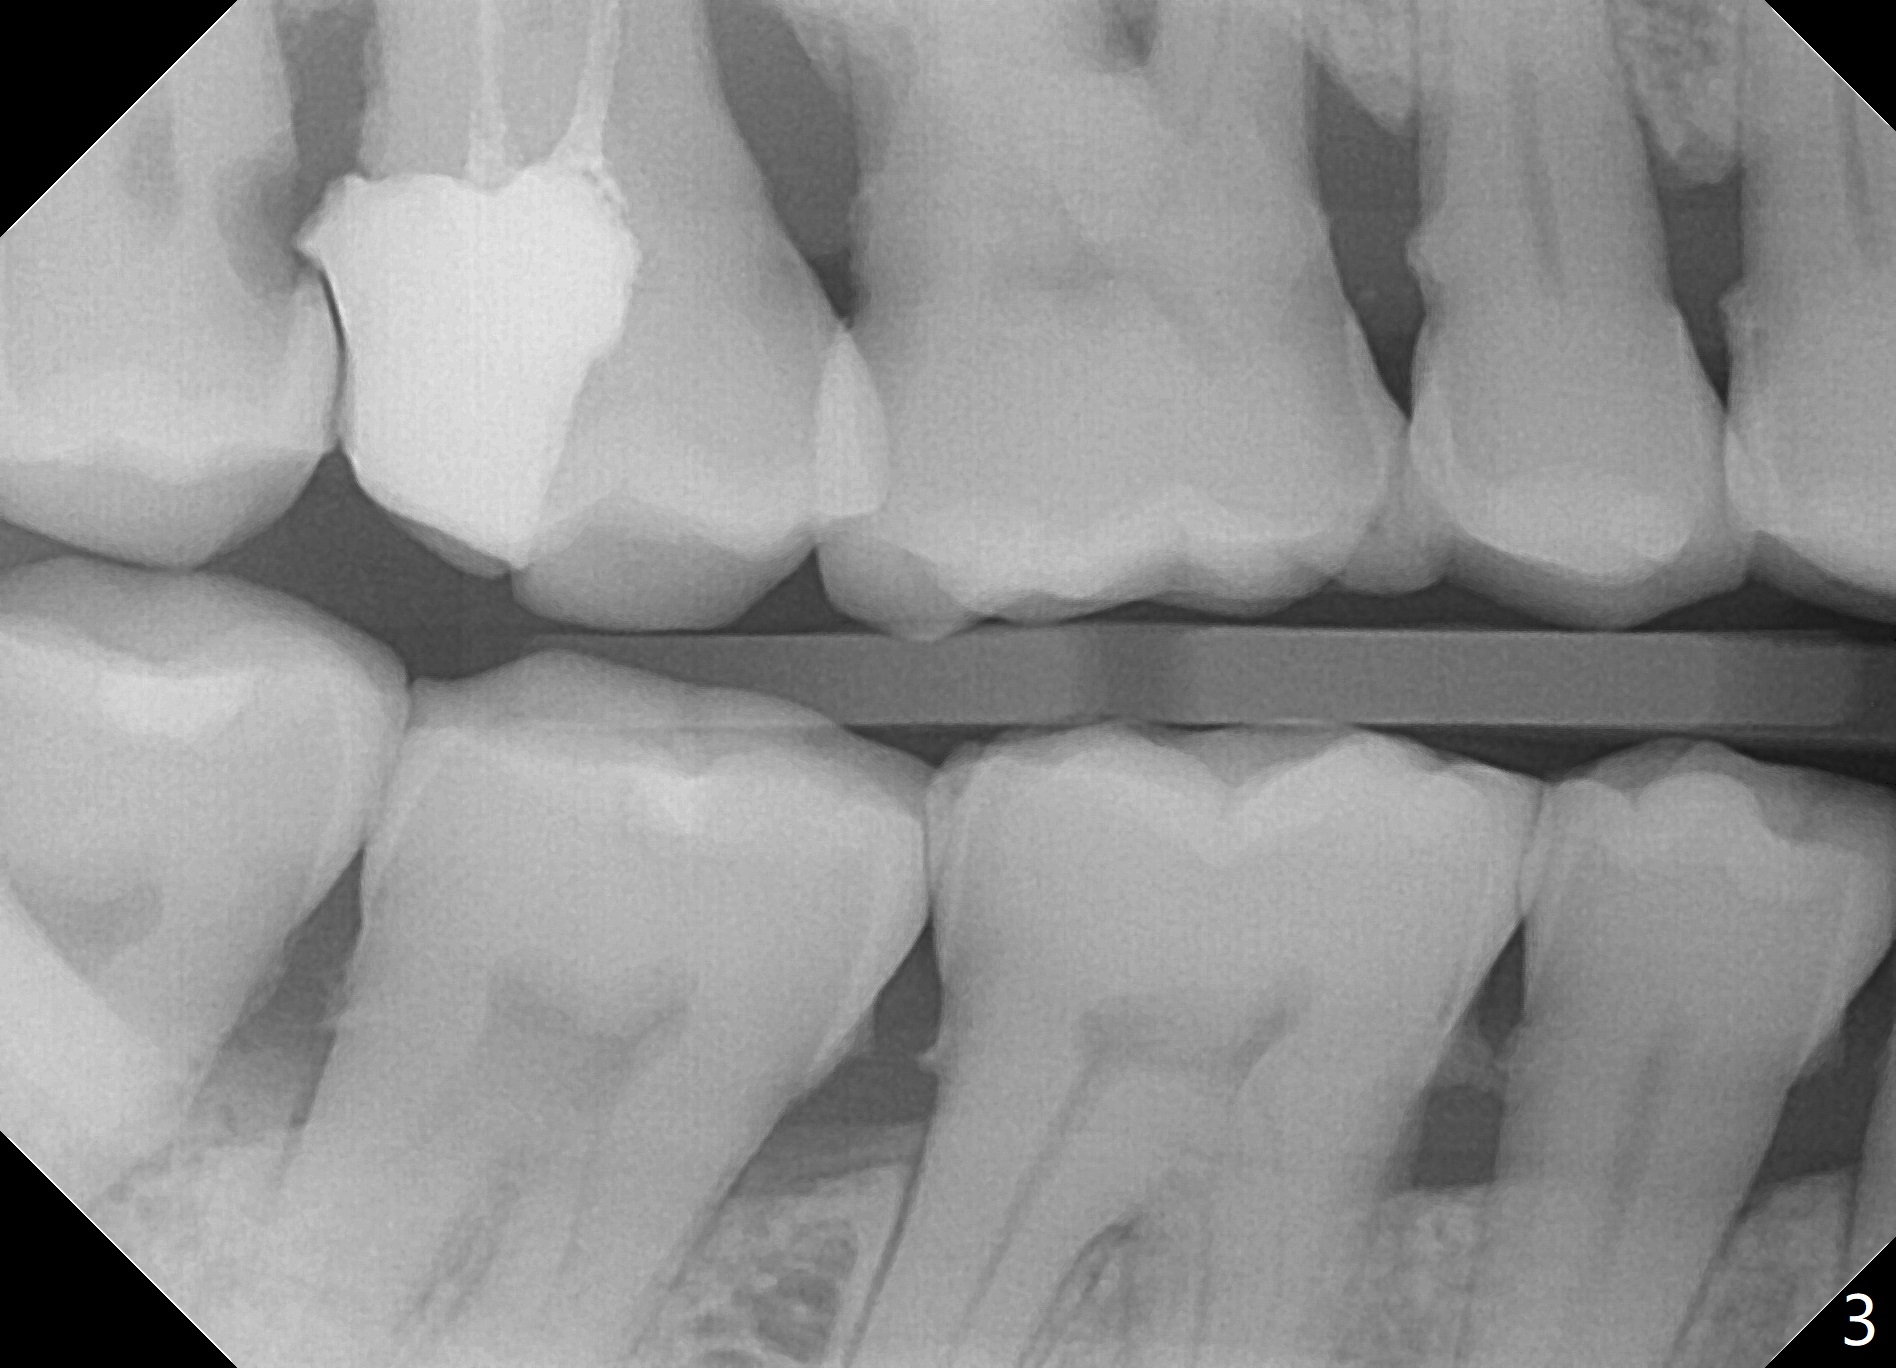

Concern of a 48-year-old woman is the exfoliating central incisor (Fig.1). After SRP (Fig.3,4), a long implant will be placed for stability (Fig.2), considering a posterior missing tooth (Fig.4).